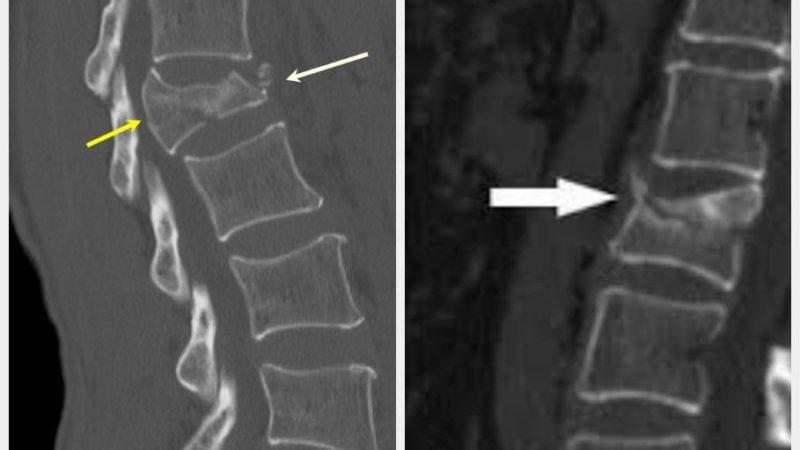

- Рентген в разных проекциях показывает наличие смещения позвонков, повреждения костей позвоночника.

- Компьютерная томография выявляет состояние деталей перелома, повреждения мягких тканей и прилежащих органов.